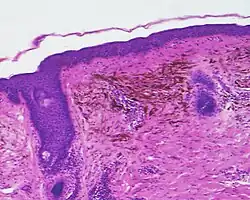

Micrograph of a blue nevus showing the characteristic pigmented melanocytes between bundles of collagen. H&E stain.

Epithelioid blue nevus